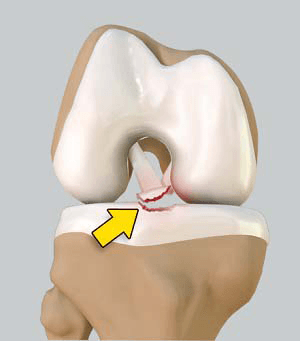

Las espinas tibiales son salientes óseos situadas en la tibia. Existen dos espinas tibiales: la espina interna o medial, donde se inserta (se ancla) el ligamento cruzado anterior y la raíz anterior del menisco externo a la tibia, y la espina tibial externa o lateral, donde se inserta el menisco externo en su raíz posterior. La función de las espinas es estabilizar a los meniscos y ligamentos en la rodilla.